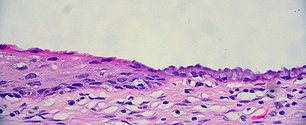

Epithelial tissues are formed by cells that cover surfaces (e.g. skin) and line tubes and cavities (e.g. digestive organs, blood vessels, kidney tubules and airways). Epithelial tissue usually consists of a single cell layer of cells, however in certain cases there may be more than one layer. All epithelial tissues are free surfaces attached to the underlying layers of a basement membrane.

There are different types of epithelial tissue which are named according to the number of layers they form and the shape of the individual cells that make up those layers. Simple epithelium refers to a single layer of cells. Stratified epithelium refers to two or more layers of cells. Squamous epithelium refers to flattened cells, cuboidal epithelium refers to cells that are cube-shaped and columnar epithelium refers to vertically elongated cells. Ciliated epithelium refers to epithelial cells that contain many tiny hair-like projections.

Pseudostratified epithelium refers to epithelium consisting of one layer but looking as though it consists of more than one layer.

The different types of epithelial tissue found in mammals.